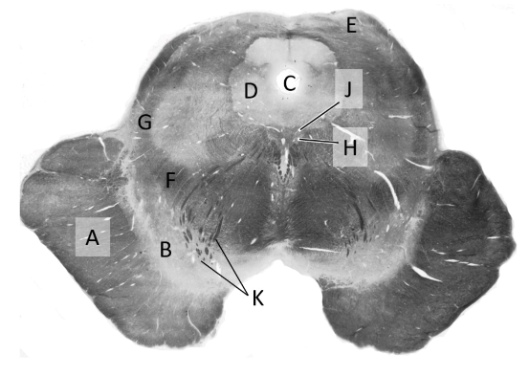

at what level is this?

lower medulla

what is a?

pyramid/ pyramidal tract (lm)

what is b?

spinal trigeminal nucleus (lm)

what is c?

trigeminal tract (lm)

what is d?

nucleus gracilis

what is e?

nucleus cuneatus (LM)

what is f?

internal arcuate fibres

what is g?

medial lemniscus (lm)

what is h?

inferior olivary nucleus (lm)